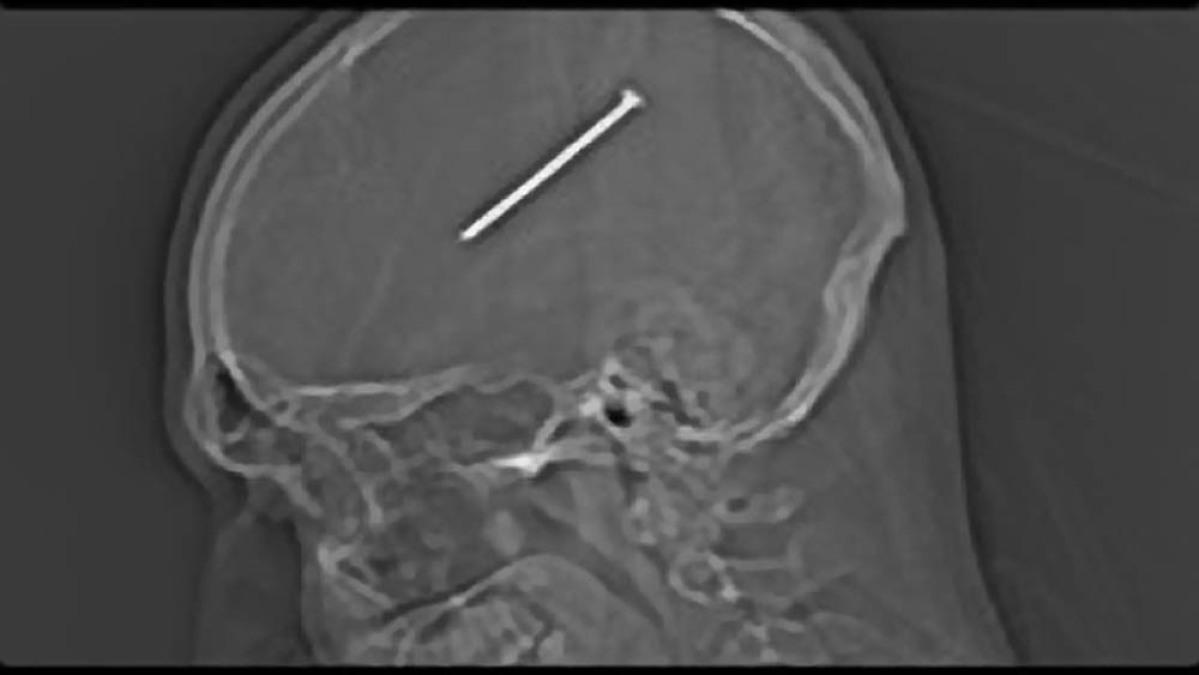

From www.sciencephoto.com

Nail in Brain, Xray Stock Image C030/6318 Science Photo Library Nail In The Head Man Don't try to fix it. The suburban chicago man was sure he’d merely cut himself with a nail gun while building a shed. I just need you to listen. every man has heard these words. The injury changed his personality, and our understanding of the brain. I just need you to listen. every man has heard these. It's not about. Nail In The Head Man.

Nail in Brain, Xray Stock Image C030/6319 Science Photo Library Nail In The Head Man A reddit post has gone viral after a man had accidently shot a nail in his. Don't try to fix it. The suburban chicago man was sure he’d merely cut himself with a nail gun while building a shed. It's not about the nail. Don't try to fix it. I just need you to listen. every man has heard these.. Nail In The Head Man.

From www.nejm.org

Nail in the Brain NEJM Nail In The Head Man I just need you to listen. every man has heard these. I just need you to listen. every man has heard these words. The suburban chicago man was sure he’d merely cut himself with a nail gun while building a shed. A reddit post has gone viral after a man had accidently shot a nail in his. It's not about. Nail In The Head Man.

From 7news.com.au

Incredible X ray shows nail stuck in man's head 7NEWS Nail In The Head Man It's not about the nail. I just need you to listen. every man has heard these. The injury changed his personality, and our understanding of the brain. A reddit post has gone viral after a man had accidently shot a nail in his. Don't try to fix it. I just need you to listen. every man has heard these words.. Nail In The Head Man.